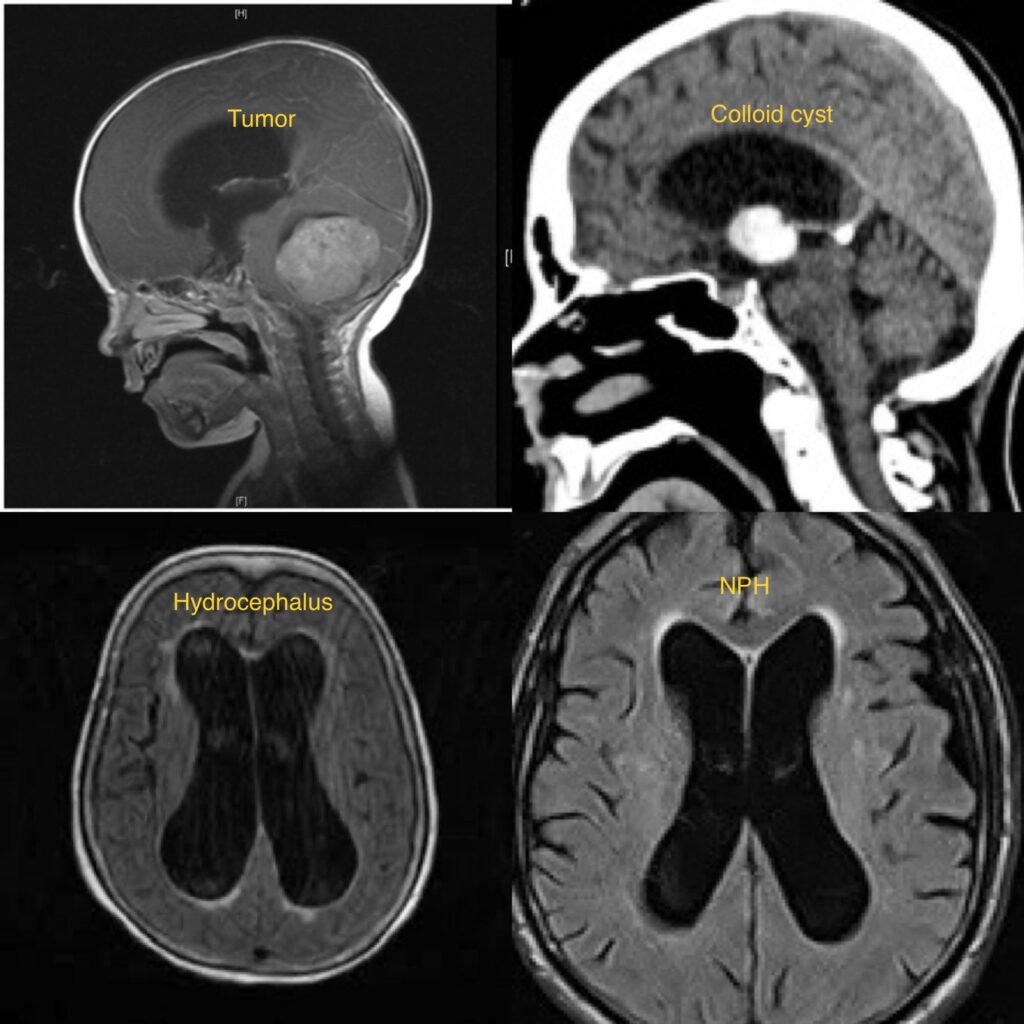

Ventricular Brain Tumors are abnormal growths of cells that develop within the ventricular system of the brain. The ventricles are fluid-filled spaces within the brain that produce and circulate cerebrospinal fluid (CSF). Tumors that arise within these ventricles can interfere with the production and flow of CSF, leading to increased pressure within the brain and potential neurological symptoms.

- Diagnosis typically involves a thorough neurological examination, medical history, imaging studies such as MRI or CT scans, and sometimes lumbar puncture (spinal tap) to evaluate CSF pressure and composition.